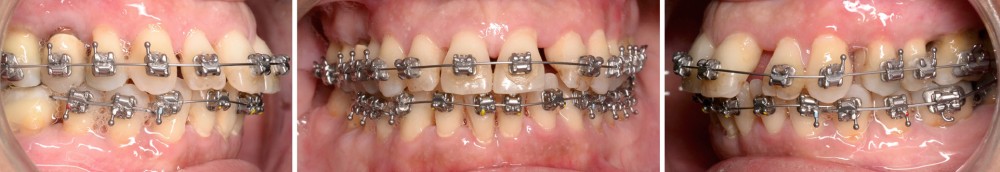

À l’examen endo-buccal (fig. 2), on note une formule dentaire complète (absence des 8) avec présence de restaurations multiples étanches, un bon contrôle de plaque et une parodontite de stade 4 grade C stabilisée [3], des récessions gingivales et des mobilités dentaires généralisées (degré 2, classification de Miller). L’arcade mandibulaire présente une courbe de spee importante avec égression du bloc incisivo-canin. Les milieux inter-incisifs sont alignés, le recouvrement est normal, le surplomb est augmenté à 3 mm et associé à des diastèmes et de la vestibulo-version des incisives maxillaires. Les relations antéro-postérieures canine et molaire sont en Classe I d’Angle.

Le traitement d’orthodontie est réalisé en technique multi-attache vestibulaire (TGO, GC Corporation, Tokyo, Japon). La dent 46 n’est pas prise en charge dans l’appareillage, étant donné son faible ancrage et son pronostic réservé. L’alignement initial est effectué sur un arc Niti .016 au maxillaire et en trois segments à la mandibule (Niti .018x.025 en postérieur et Niti .016 de 33 à 43) (fig. 6).